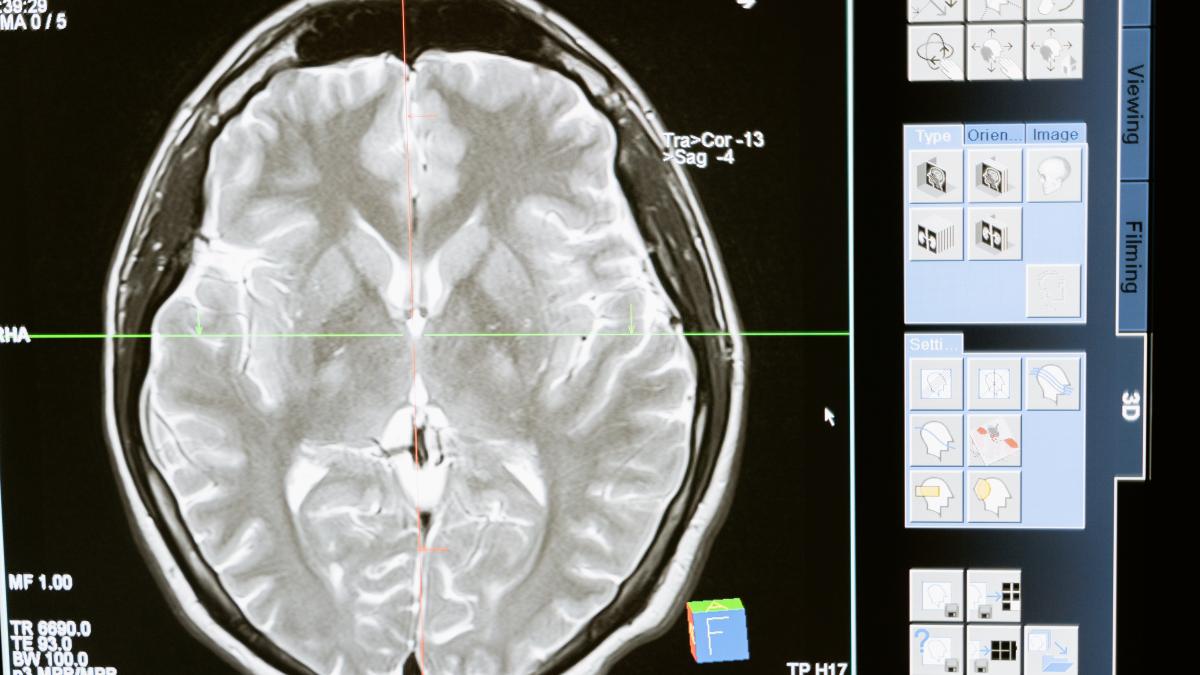

leziuni-cerebrale--pacientul-m_62113800 Fotografie de la Mehmet Turgut Kirkgoz/ Pexels

Potrivit medicului, glonțul a afectat parțial cortexul cerebral în regiunea parieto-occipitală stângă, a cărei activitate principală este procesarea vederii. Pacientul M. a fost studiat de Gonzalo până la moartea sa în 1986: un studiu care a durat 50 de ani și care ne-a permis să aruncăm lumină asupra funcționării creierului uman.